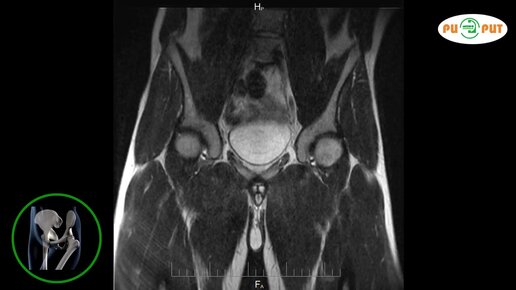

Как делают МРТ тазобедренных суставов (видео)